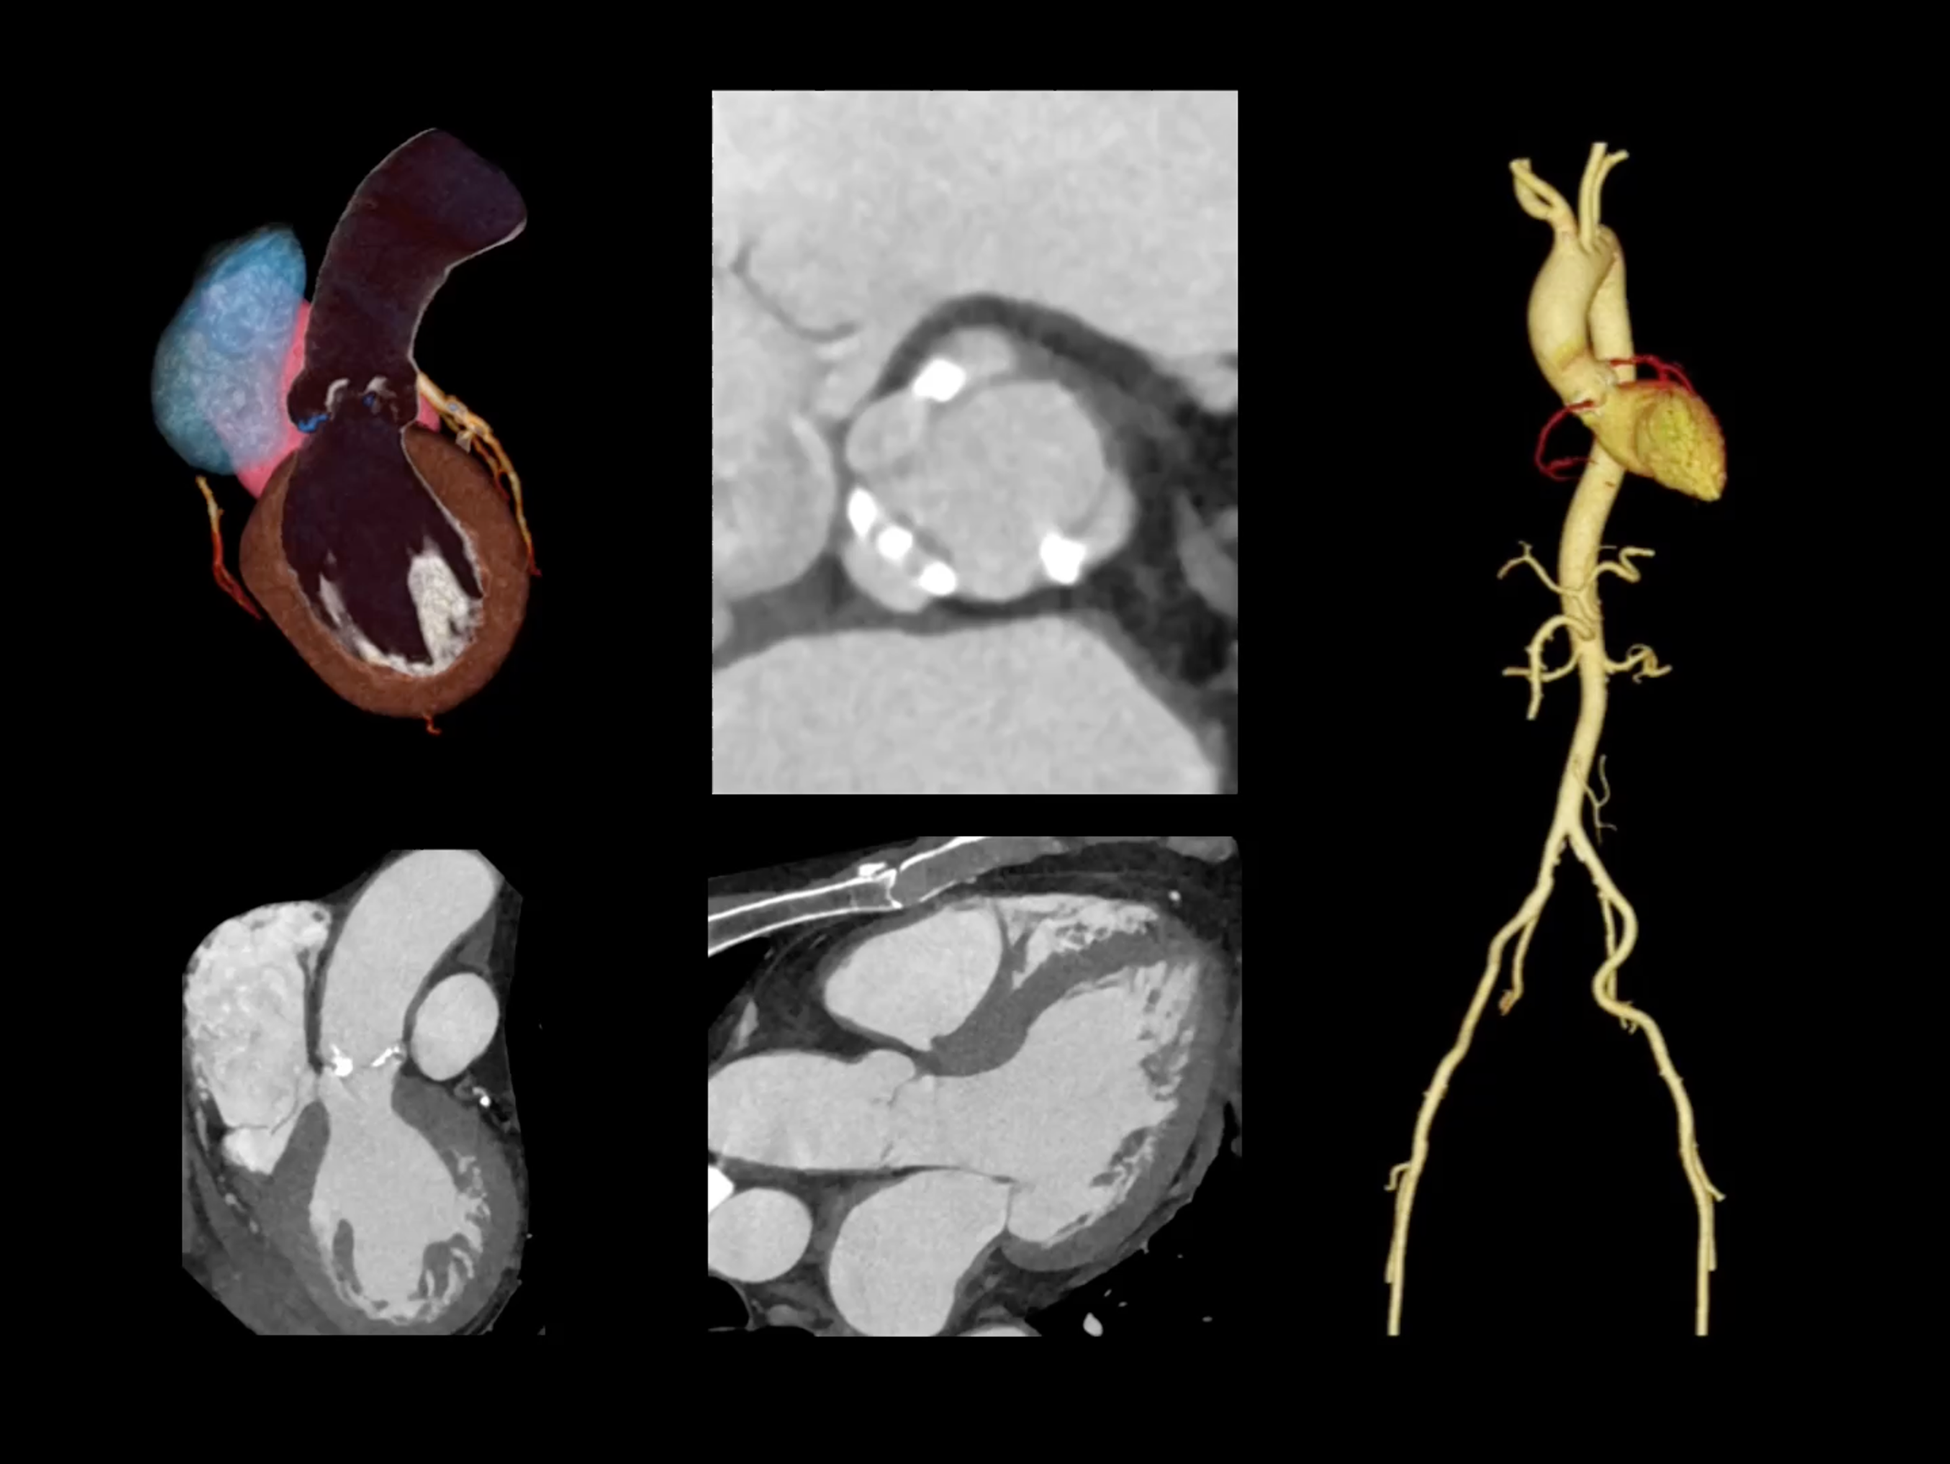

全心4D电影成像

提供全心动周期内多个时相的清晰结构成像信息,动态展示心脏结构运动变化。

一站式心脏多维成像

一次对比剂注射可同时获取冠脉CTA、心肌灌注和心肌延迟强化等多维图像信息。

全域能谱

uCT SiriuX® 依托16cm超宽探测器与双源能谱技术,实现真正意义上的全身高清能谱成像。单次扫描同步获取灌注、能谱等多维定量参数,精准解析组织特性与病灶成分,为临床决策提供更深层次的诊断依据。

全身高清能谱成像

uCT SiriuX® 采用独有的双宽体探测器设计,实现470mm超大视野与全脏器容积覆盖的能谱成像,轻松应对不同体型患者和扫描部位应用需求。配合创新能谱重建影像链与精准双能数据配准,系统可有效抑制伪影、提升信噪比,在全脏器范围内提供高质量能谱图像,显著拓展临床精准诊断的广度与深度。